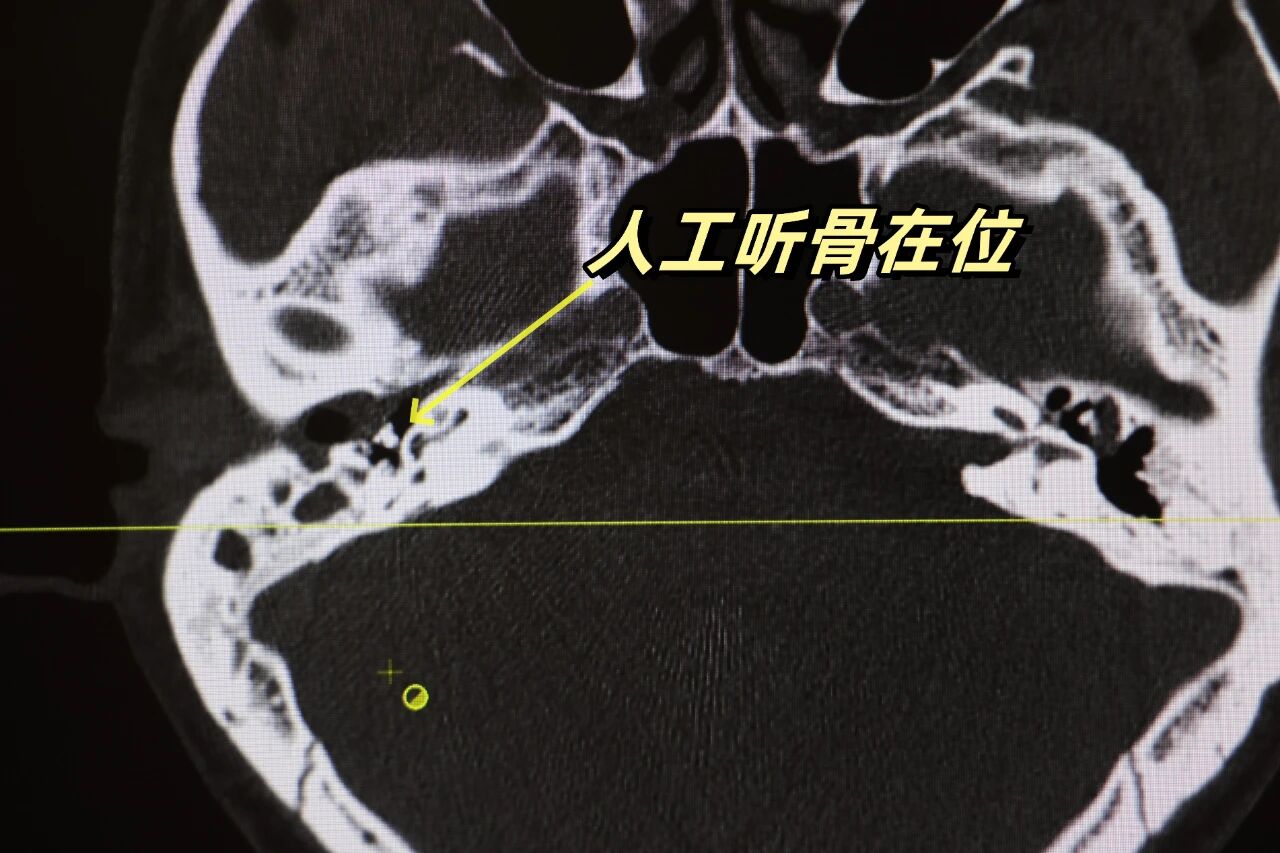

经过周密的术前准备,张传海主任带领手术团队,凭借扎实的专业知识和娴熟的操作技巧,为周先生成功实施了微创耳内镜下右耳鼓室成形术+人工听骨植入术。

术中探查见鼓膜松弛部内陷袋及胆脂瘤上皮,清除后发现上鼓室骨质已有吸收,胆脂瘤经松弛部穿孔进入鼓室,并已侵蚀破坏部分听小骨。清除胆脂瘤完全,并成功植入人工听骨,成功完成了听骨链的重建。

术后周先生顺利出院。一月后返院复查:诉听力明显提高。